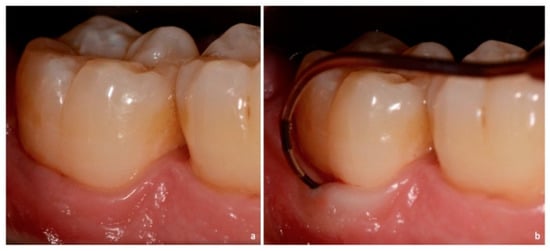

Figure 4. Non-exposed furcation lesion—Class II (NEII): (a) Second mandibular molar; (b) Buccal furcation lesion. Horizontal attachment loss of 4 mm.

Class II: partial horizontal bone loss. The examiner probe penetrates three millimeters or more from the entrance of furcation, but there is not a total attachment loss with a through and through opening of the furcation (Figure 4 and Figure 8).